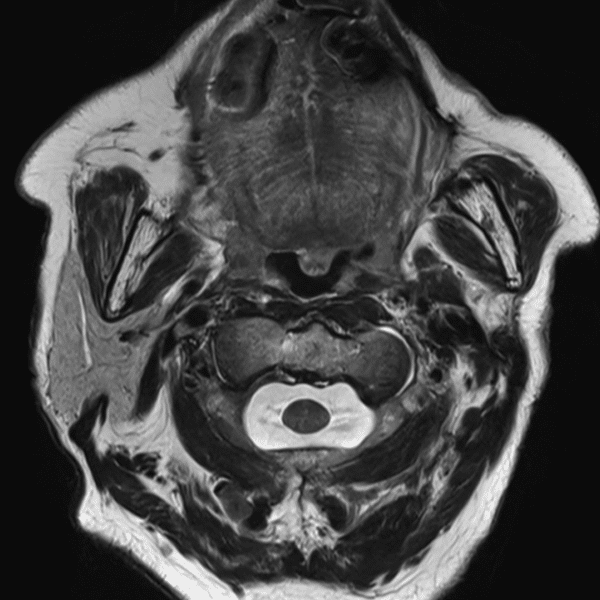

Neck T2WI

3.0T Siemens MAGNETOM Skyra

2D TSE

(L) 0.5×0.7×3.0 mm

(R) 0.4×0.6×3.0 mm

Conventional SwiftMR™ 02:50 01:17 (55% Faster)